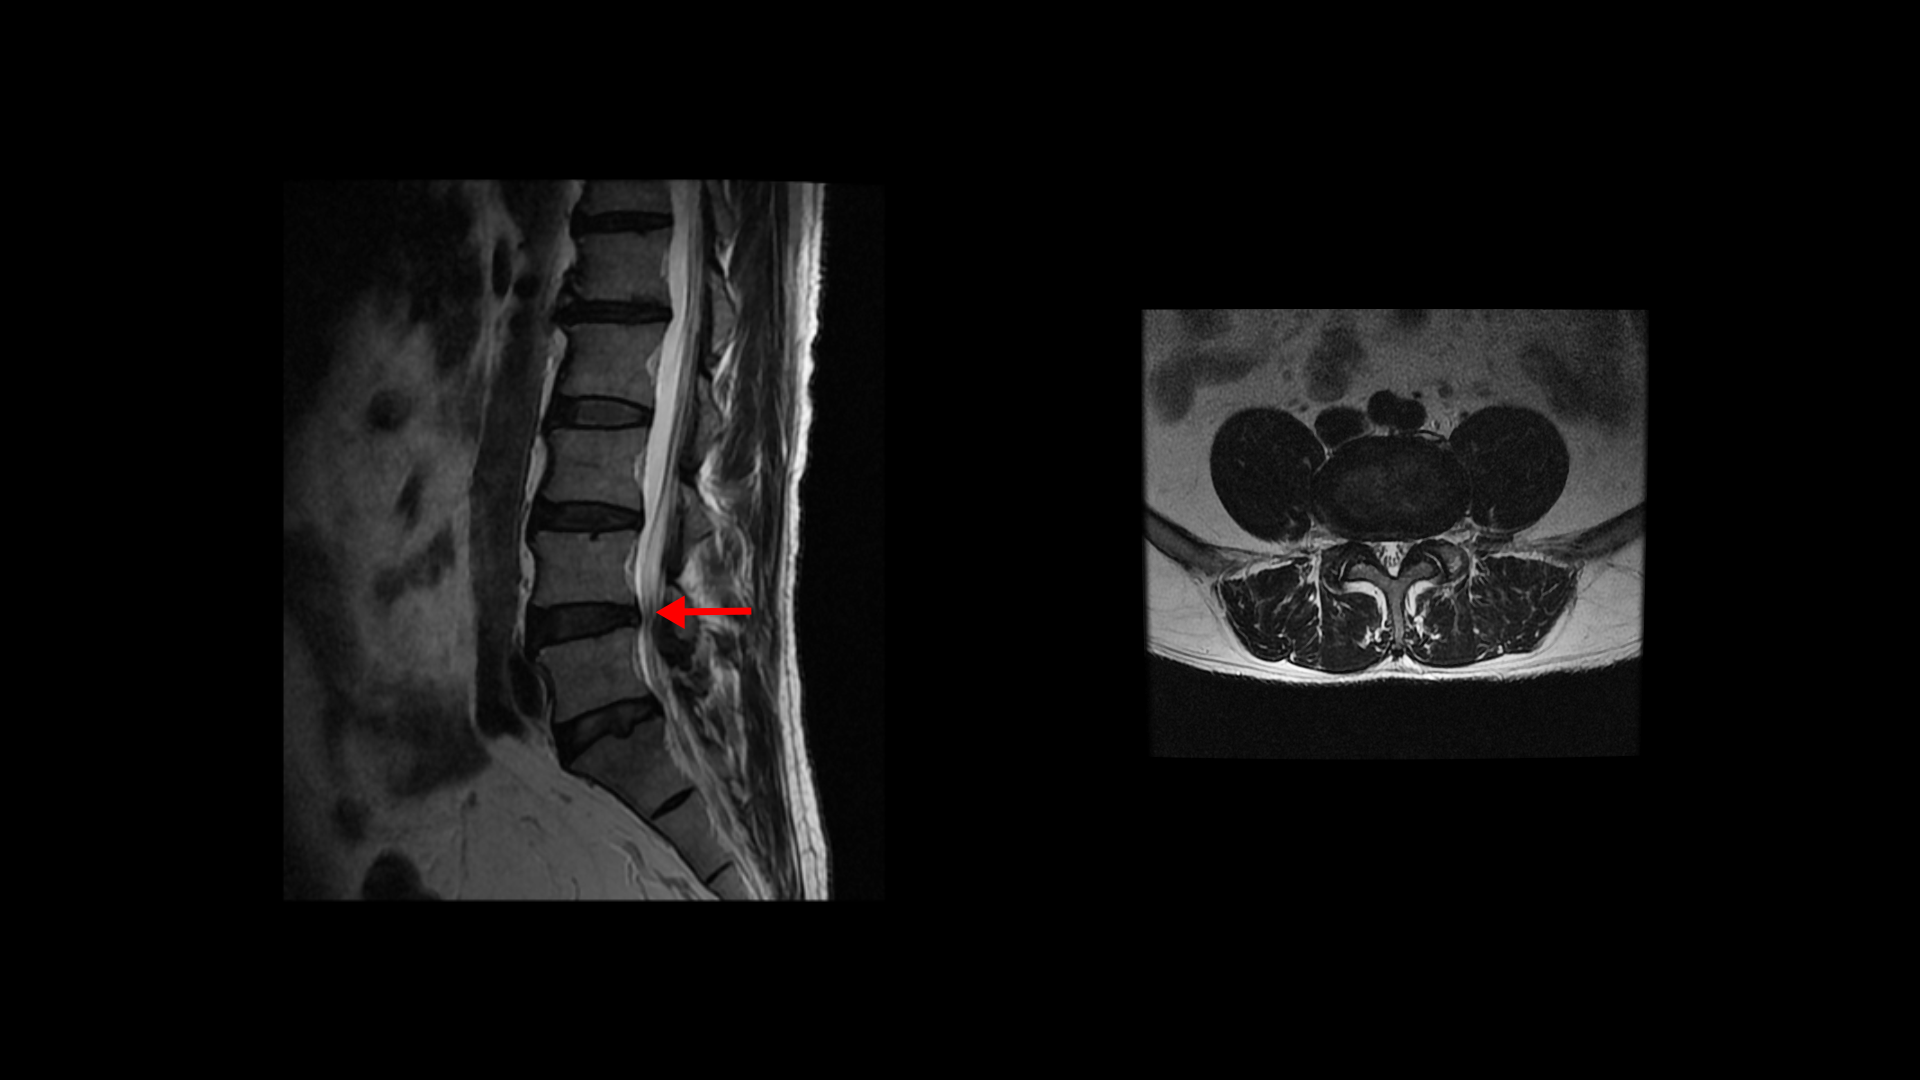

특히 MRI에서 보이는 신경 눌림이 심하지 않을수록 근육 문제일 가능성은 훨씬 더 높아집니다. 이 환자분 MRI를 한번 볼까요? 세 마디에 퇴행성 디스크가 있지만 심하지 않습니다.

4번 5번 마디의 척추관도 협착이 진행되었지만 좁아진 게 많이 심하지 않습니다.

오른쪽, 왼쪽 신경이 빠져나가는 추간공도 조금 좁아지긴 했지만 별로 심하지 않습니다.